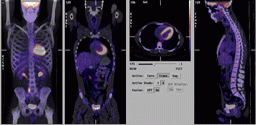

March 26, 2010 - For a patient with heart failure, checking whether the heart could benefit from bypass surgery or a stent is critical to ensuring survival. One imaging technique, positron emission tomography (PET) with the imaging agent fluorodeoxyglucose (FDG), may provide doctors with the information they need to make more informed treatment decisions, according to research published in the April issue of The Journal of Nuclear Medicine (JNM).

The study reported in JNM is a substudy of one of the first investigations to prospectively gather evidence in a structured randomized research protocol. The benefits of using FDG PET to assess myocardial viability—to find whether heart tissue is likely to benefit from revascularization, or restoring blood flow to the heart in order to restore impaired pumping capacity—have long been observed.

Researchers in Ottawa, Canada, analyzed data from a study that used FDG PET-directed management versus standard clinical management of patients with coronary artery disease and poor left ventricular function. The report showed that FDG PET can be a useful tool for identifying patients who would benefit from bypass surgery or other procedures to improve blood flow.

Cardiovascular disease remains the number one cause of death in the United States. Surgery to repair damage and restore blood flow to the heart can help some patients with congestive heart failure before it is too late. Although other imaging techniques simply characterize heart tissue as being dead (scarred) or alive (viable), molecular imaging gives doctors a more complete picture of how the heart is working, including the rate of blood flow and the metabolism of the heart. Reduced blood flow could be a sign of blocked arteries; maintained metabolism means the heart tissue in this region is still viable and would benefit from restoring flow to normal. With this information, doctors should be able to better plan treatments—and heart disease patients should have better outcomes.